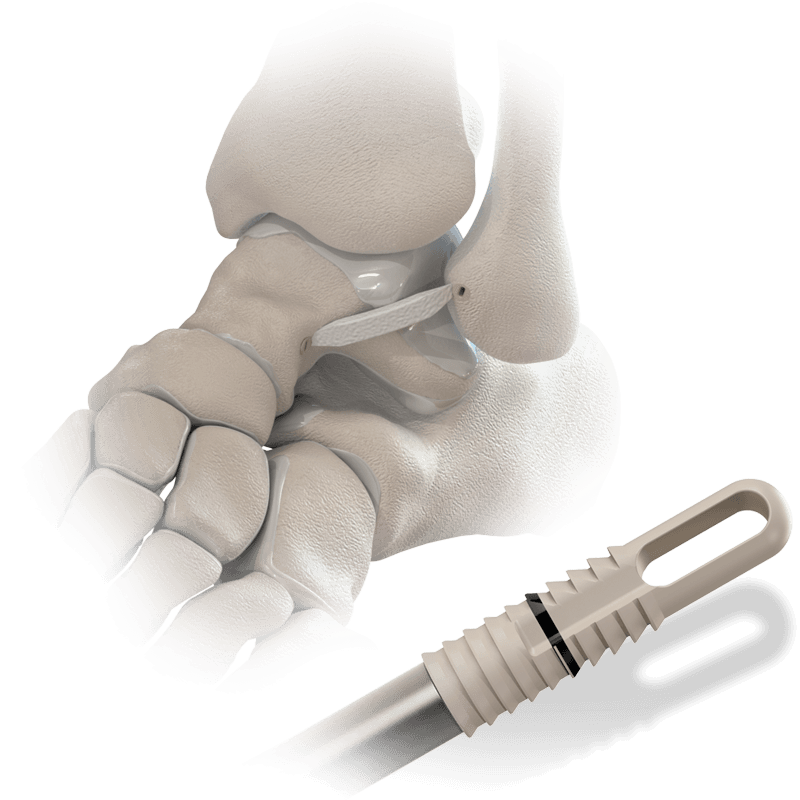

Hercules® XE Knotless Anchor for BioBrace®

A radiolucent PEEK anchor with the extended eyelet, designed for use with the BioBrace® 5x250mm scaffold in complex foot and ankle repairs.

Applications:

- Lateral and medial ankle instability

- Achilles tendon and Metatarsal ligament repair

- Midfoot reconstruction

- Hallux valgus correction

Key Advantages:

- Available in 3.5mm 4.5mm, and 5.5mm sizes

- Compatible with BioBrace® scaffold for biologic reinforcement

- Enables dual-anchor deployment for ligament/tendon augmentation

- Delivered sterile and pre-assembled